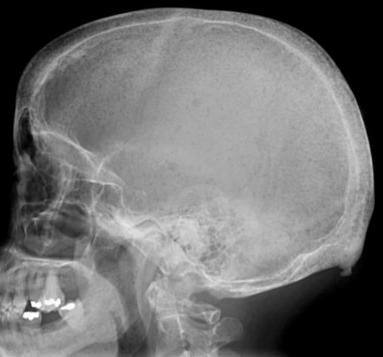

Thalassemia

• Extramedullary hematopoiesis

• Prominent marrow expansion (appears as thick bones)

• Generalized bone demineralization

Hyperparathyroidism

• Salt & pepper skull